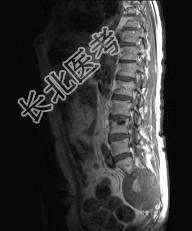

- 多项选择题常见的椎管内肿瘤(如图所示)有 ( )

A、脊膜瘤

B、胶质瘤

C、血管瘤

D、上皮样囊肿

E、神经鞘瘤